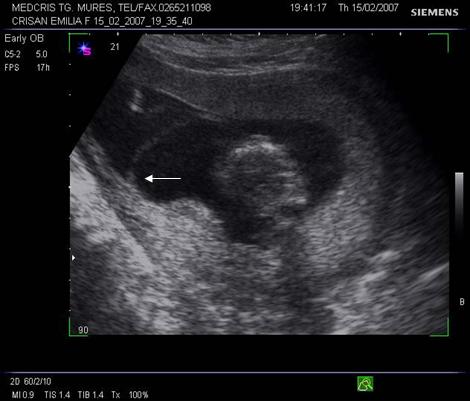

Fig nr 36 Sarcina gemelara biamniotica, 6 sapt, cu 2

saci amniotici si 2 embrioni (cu sageata )

Fig nr 37. Aceeasi sarcina gemelara de 6 sapt., sectiune fara embrioni,cu sacii amniotici caracteristic dispusi in ochi de bufnita